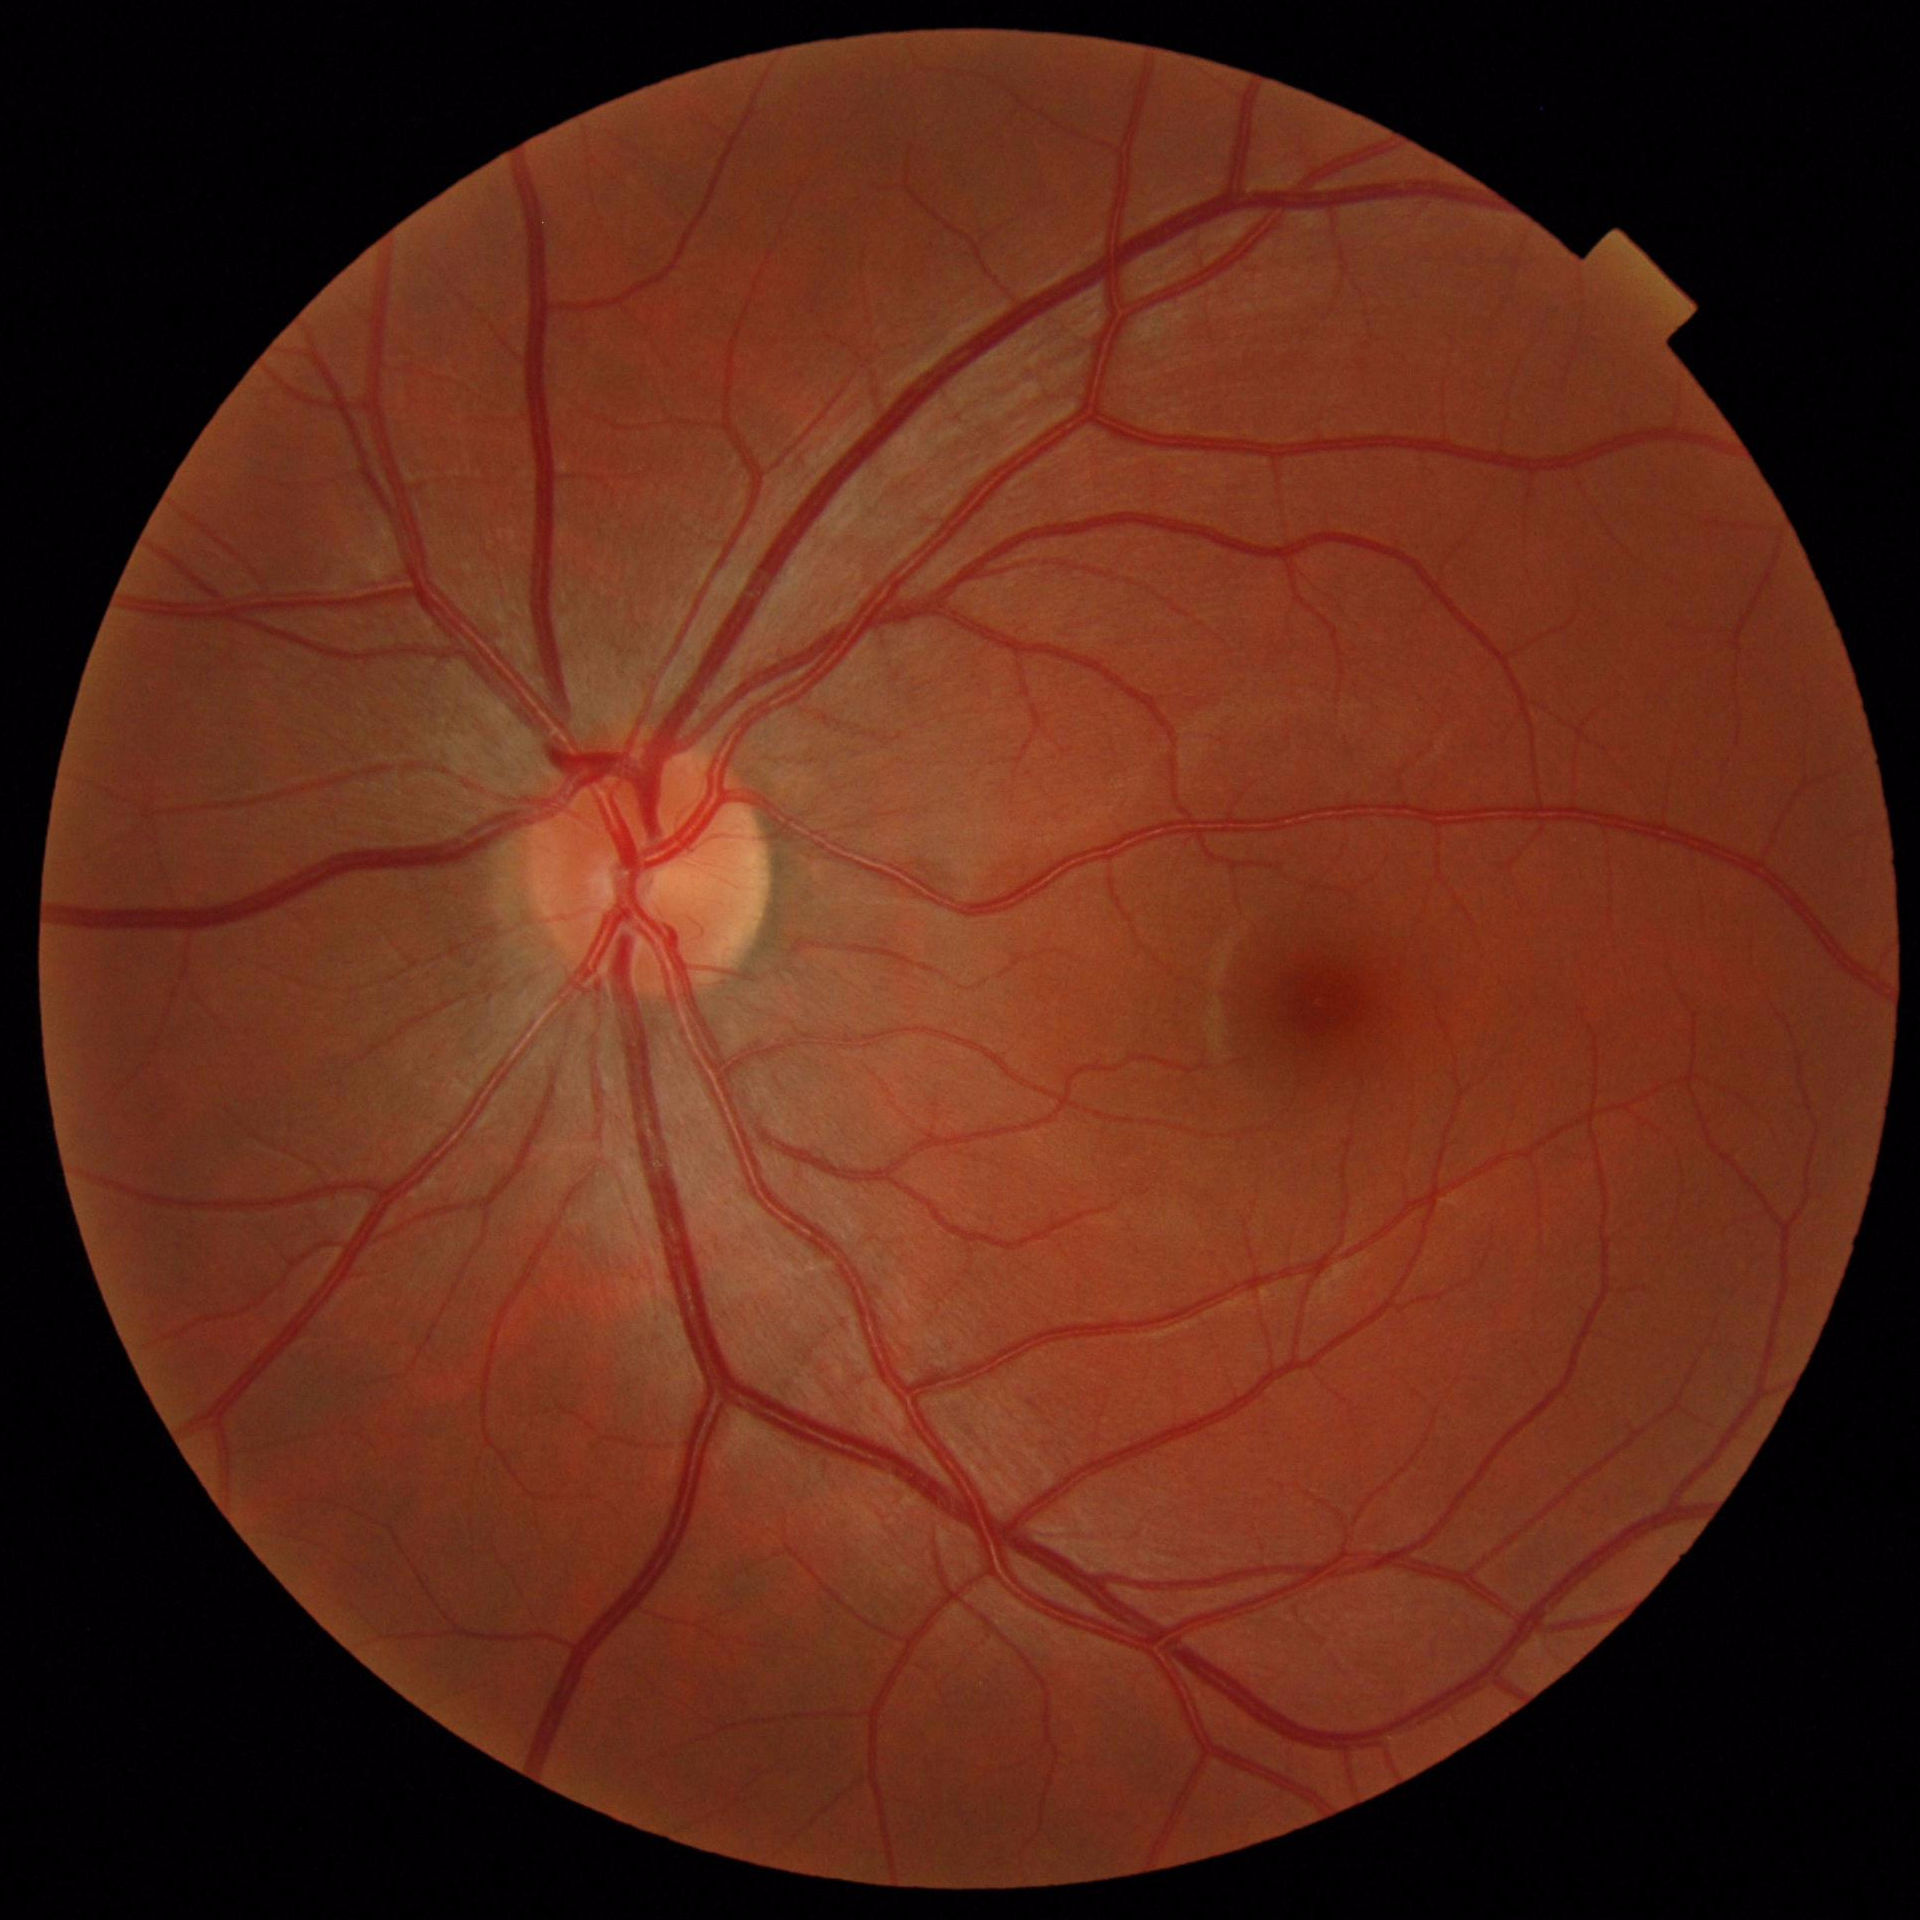

VI Evaluation

To put our results into perspective, Table V compares previous works to our methods. We report the -score for our results together with their standard deviation. Overall M2U-Net and DRIU trained on COVD are competitive, with the best performance on the high-resolution dataset HRF, where a new state-of-the-art F1-score could be reached. Additional metrics such as accuracy, sensitivity, precision and specificity are available in the documentation of our software package. Further, to the available public datasets, we trained M2U-Net on COVD for a private target dataset with a resolution of 1920x1920 for which no ground-truth data is available. The predicted vessel probability maps are displayed in Figure 5. While we can only make subjective statements, we find that the generated probability maps are of good quality, with the majority of main vessels being detected, even in presence of pathologies. An illustration of predicted vessel maps versus ground truths for M2U-Net on HRF is provided in Figure 4.

The authors would like to thank Dr. Christophe Chiquet from the University Hospital of Grenoble and Inserm, France, for providing the high-resolution retina fundus images in Fig. 5.